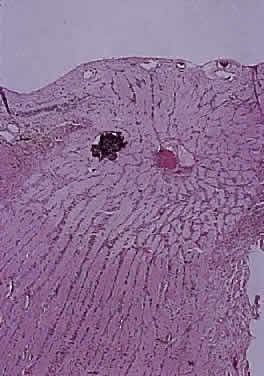

Fig. 3. Cross-section of normal optic nerve, showing central vessels within common thin-walled pial strand. Thin pial strands divide nerve into fascicles. Meningeal sheath is closely applied to optic nerve (hematoxylin and eosin staining).